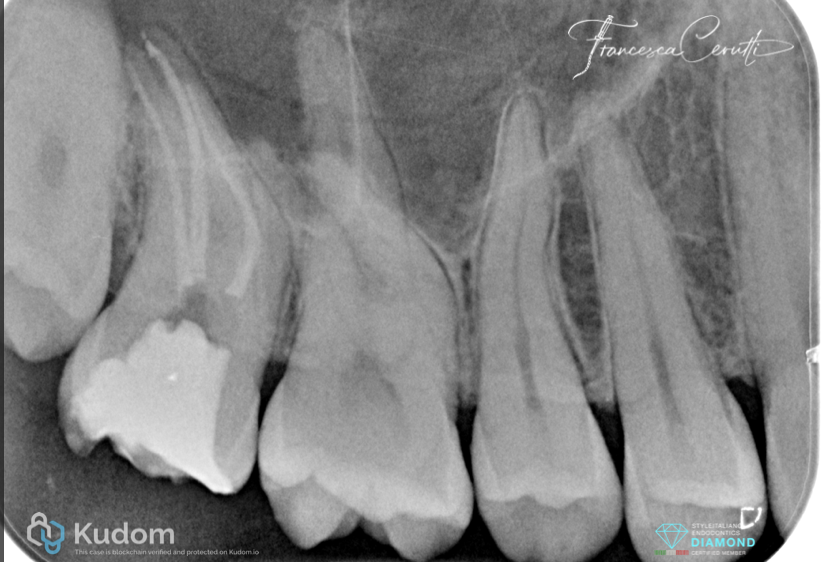

Post operative X-ray

Fig. 14

Follow up X-ray